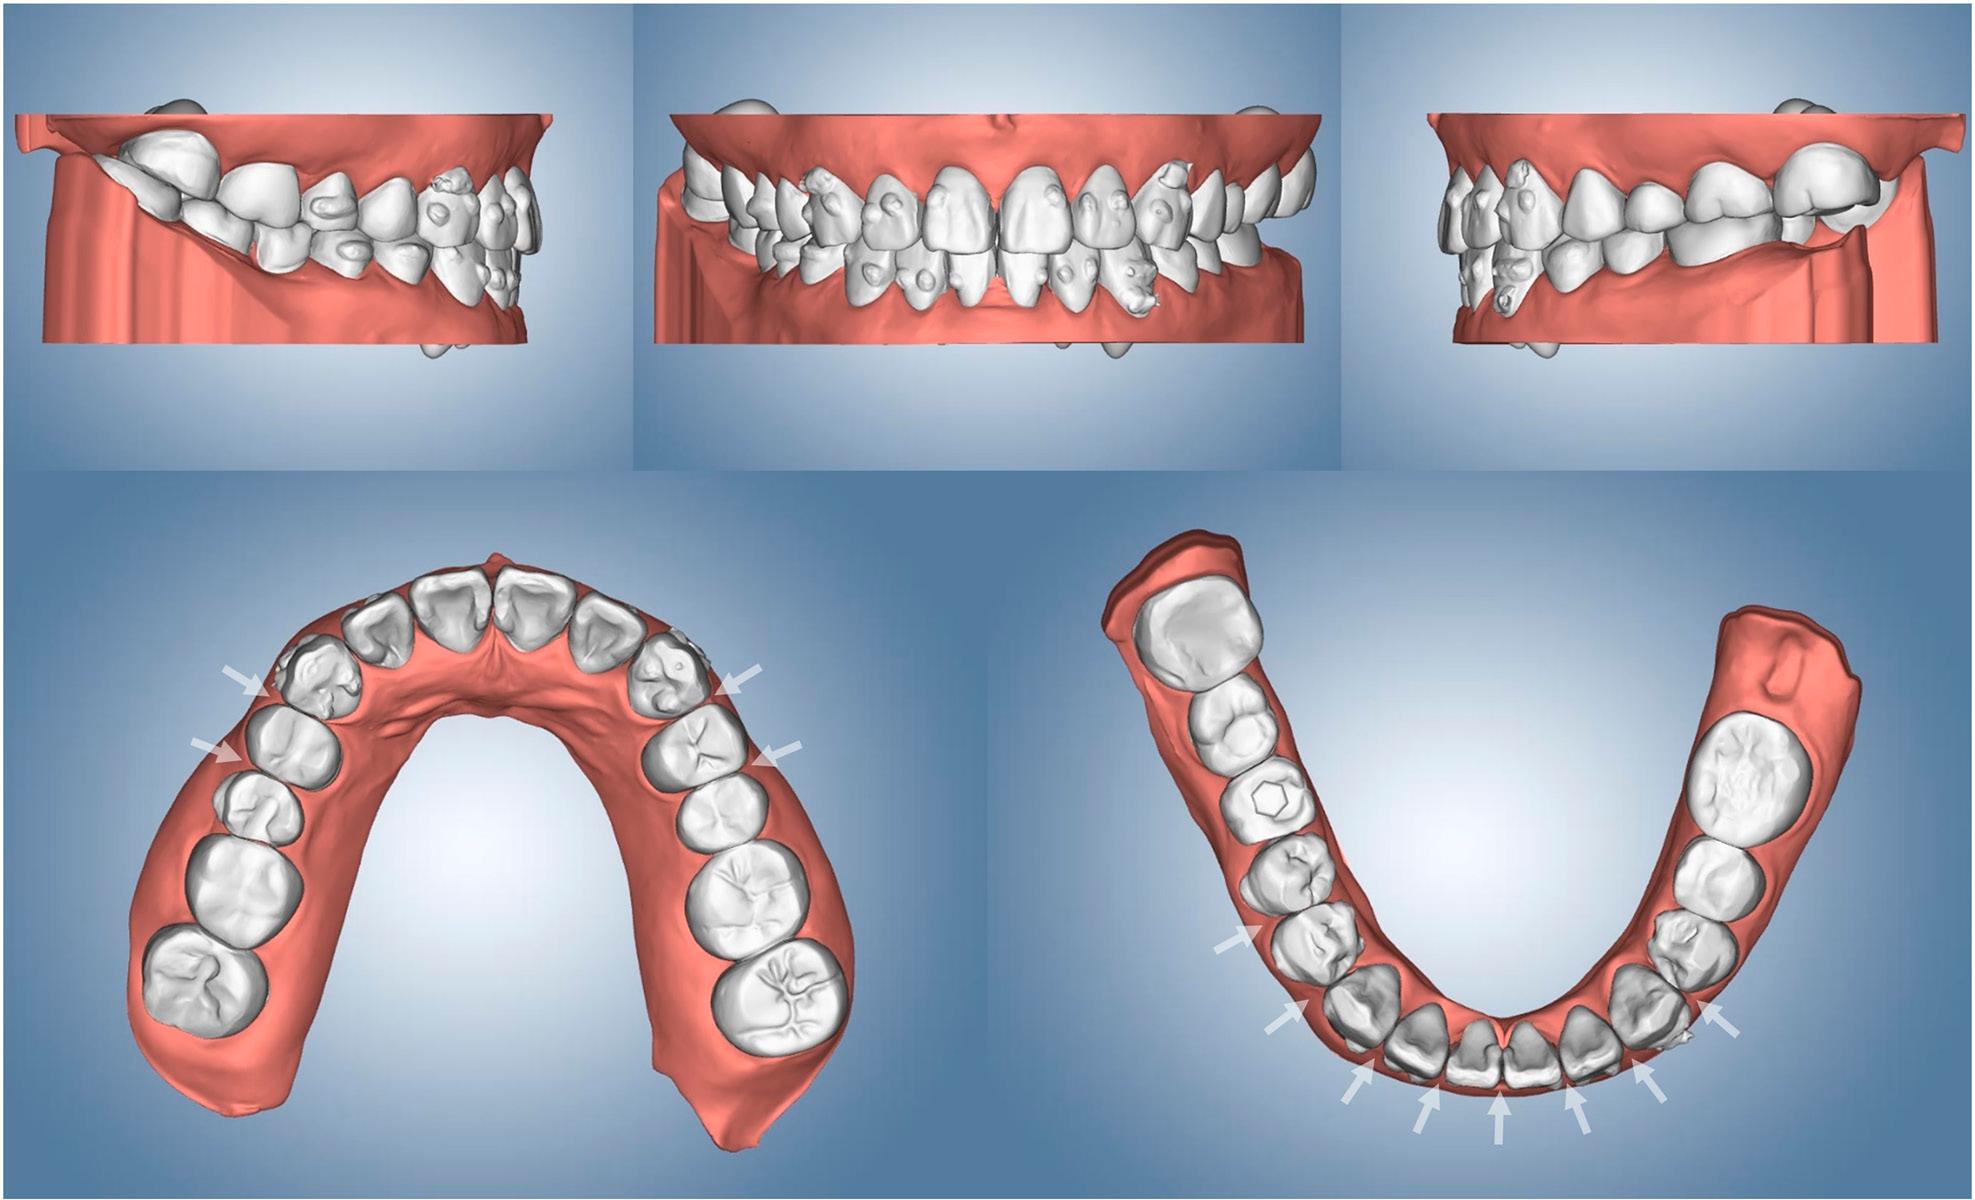

Figure 3.

Figure 4.